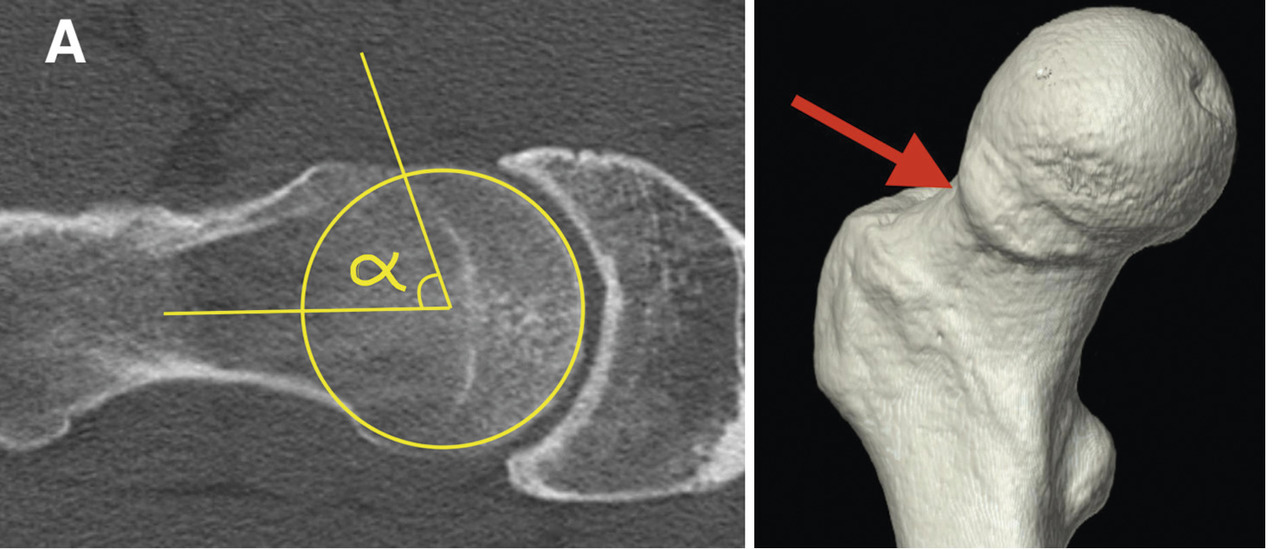

Les radios standard comportent des clichés du bassin, face et profil (bassin de face debout en charge). On peut voir un effet pince avec une éventuelle rétroversion acétabulaire, une coxa profunda avec protrusion acétabulaire. L’effet came est recherché en incidence spécifique : le profil de Dunn à 45°. Il déroule le col fémoral pour mettre en évidence sa « bosse » et la perte de sphéricité de la tête (fig. 3). On peut ainsi calculer l’angle alpha, norma-lement inférieur à 50°. Au-delà de 50°, il y a conflit par effet came.

L’association de symptômes douloureux et de radiographies évocatrices confirme le diagnostic. Une imagerie en coupes et injectée (arthroscanner ou arthro-IRM) précise les lésions cartilagineuses et labrales. Une reconstruction 3D montre la bosse fémorale en vue d’une éventuelle résection (fig. 1).